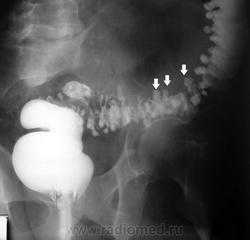

КТ с контрастированием, исследование пожилого мужчины, первые три аксиальных среза. На этом срезе через нижний отдел грудной полости визуализируется часть желудка, контрастируемая веществом, принятым внутрь. Обратите внимание на широкое окно между ножками диафрагмы, позволяющее желудку (кардиальному отделу) сместиться, на уровне щели венозной связки, в норме обозначающей пищеводно-желудочный переход. Это скользящая грыжа пищеводного отверстия. На более каудальном срезе при КТ определяется стойкое расширение отверстия между ножками диафрагмы, на этом уровне в норме соединяющимися в области срединной линии. Эзофагография, бариевый контраст: паутиноподобное сужение пищеводно-желудочного пищевода, характерное для пищеводного кольца Б, обозначающего переход между плоским и цилиндрическим эпителием. Кольцо Б также визуализируется, что обусловлено грыжей пищеводного отверстия (и использованием высококачественной рентгенографической техники), в виде расширенного дистального отдела пищевода и проксимального отдела желудка. На второй эзофагограмме этого же пациента определяются складки желудка, идущие выше диафрагмы к кольцу Б — еще один признак грыжи пищеводного отверстия. Эзофагография, бариевый контраст: сужение просвета пищеводно-желудочного перехода в области кольца типа Б. Нижнее пищеводное кольцо уплотнено, просвет пищевода сужен, что вызвано воспалением и рубцовыми изменениями, почти всегда обусловленными гастроэзофагиальным рефлюксом. Обратите внимание на сочетание с мелкой грыжей пищеводного отверстия. Сужение просвета в области кольца Б иногда называют кольцом Шацкого в честь рентгенолога, обратившего внимание на частые жалобы пациентов с этим признаком на рефлюкс и «затруднение» прохождения пищи в пищеводе, иногда требующего эндоскопического лечения. Эзофагография, бариевый контраст. На снимке в боковой проекции определяется круглое вдавление задней стенки глоточно-пищеводного перехода на уровне пространства диска между 5-м и 6-м шейными позвонками. Глотка расширена, что говорит о нарушении прохождения бария. Эти признаки характерны для спазма и ахалазии (нарушение расслабления) перстнеглоточной мышцы, являющейся частью верхнего пищеводного сфинктера. Перстнеглоточная мышца в норме расслабляется перед проглатыванием комка пищи. На снимке в боковой проекции определяется стойкое заполнение глотки и сокращение перстнеглоточной мышцы после прохождения сгустка бария. На снимке нижнего отдела грудной полости у этого же пациента определяется грыжа пищеводного отверстия. Ахалазия перстнеглоточной мышцы часто является опосредованным итогом нарушения сократимости пищевода и кислотного рефлюкса. Эзофагография, бариево-воздушный контраст. На двух снимках определяется необычная «паркетная», а не нормальная гладкая поверхность пищевода. Этот признак является приходящим, представляет собой результат сокращения мышечного слоя и обычно обусловлен эпизодами рефлюкса, «раздражающими» пищевод. Паркетоподобный характер покрытия барием встречается нечасто у людей, но, по-видимому, часто встречается в пищеводе кошек, и поэтому описывается как «кошачий» пищевод. Прицельная рентгенография верхних отделов ЖКТ с бариевым контрастом: определяется грыжевое смещение дна и кардиального отдела желудка. Этот признак соответствует околопищеводной грыже и считается более серьезным основанием для хирургического вмешательства, чем простая скользящая грыжа пищеводного отверстия, при которой вовлекается только кардиальный отдел желудка. При большинстве околопищеводных грыж (ОПГ) пищеводно-желудочный переход расположен выше диафрагмы; они классифицируются как ОПГ III типа. Грыжи, при которых пищеводно-желудочный переход расположен ниже диафрагмы, классифицируются как ОПГ II типа. Термин «околопищеводная» отражает расположение желудка в грудной полости рядом с пищеводом. Бесконтрастная КТ, корональный срез: крупная околопищеводная грыжа, желудок целиком расположен в грудной полости. На аксиальных срезах пищевод определяется вблизи желудка. Бесконтрастная КТ, корональный срез: у этого же пациента определяется выраженное зияние диафрагмального отверстия со значительным расширением межножкового отверстия, позволяющим всему желудку сместиться через окно в диафрагме. Прицельная рентгенография верхних отделов ЖКТ: у этого же пациента хорошо визуализируется желудок, полностью расположенный в грудной полости. Однако, несмотря на это, не наблюдается признаков обструкции и контрастное вещество нормально проходит из желудка в тонкую кишку. КТ с контрастированием, аксиальный срез: у пациента с диагностированным хроническим гепатитом определяется распространенное варикозное расширение околопищеводных вен, которое является «восходящим» и связано с повышением давления в полой вене и током крови от печени в ее обход. КТ с контрастированием, аксиальный срез: у этого же пациента определяется распространенное варикозное расширение околожелудочных и околоселезеночных вен верхнего отдела брюшной полости, сочетающееся с портальной гипертензией. Обратите внимание на цирротические изменения печени, включая гипертрофию хвостатой доли, мелкобугристую поверхность и расширение перипортального пространства. КТ с контрастированием, объемная реконструкция, корональный срез: несколько типичных локализаций коллатеральных сосудов у пациентов с портальной гипертензией, включая варикозное расширение пищеводных, околожелудочных и околоселезеночных вен. Левая почечная вена значительно расширена и сообщается с околоселезеночными и селезеночными варикозно расширенными венами, что сочетается с селезеночно-почечным шунтом. Обратите внимание на значительное увеличение селезенки, что также обусловлено портальной гипертензией.